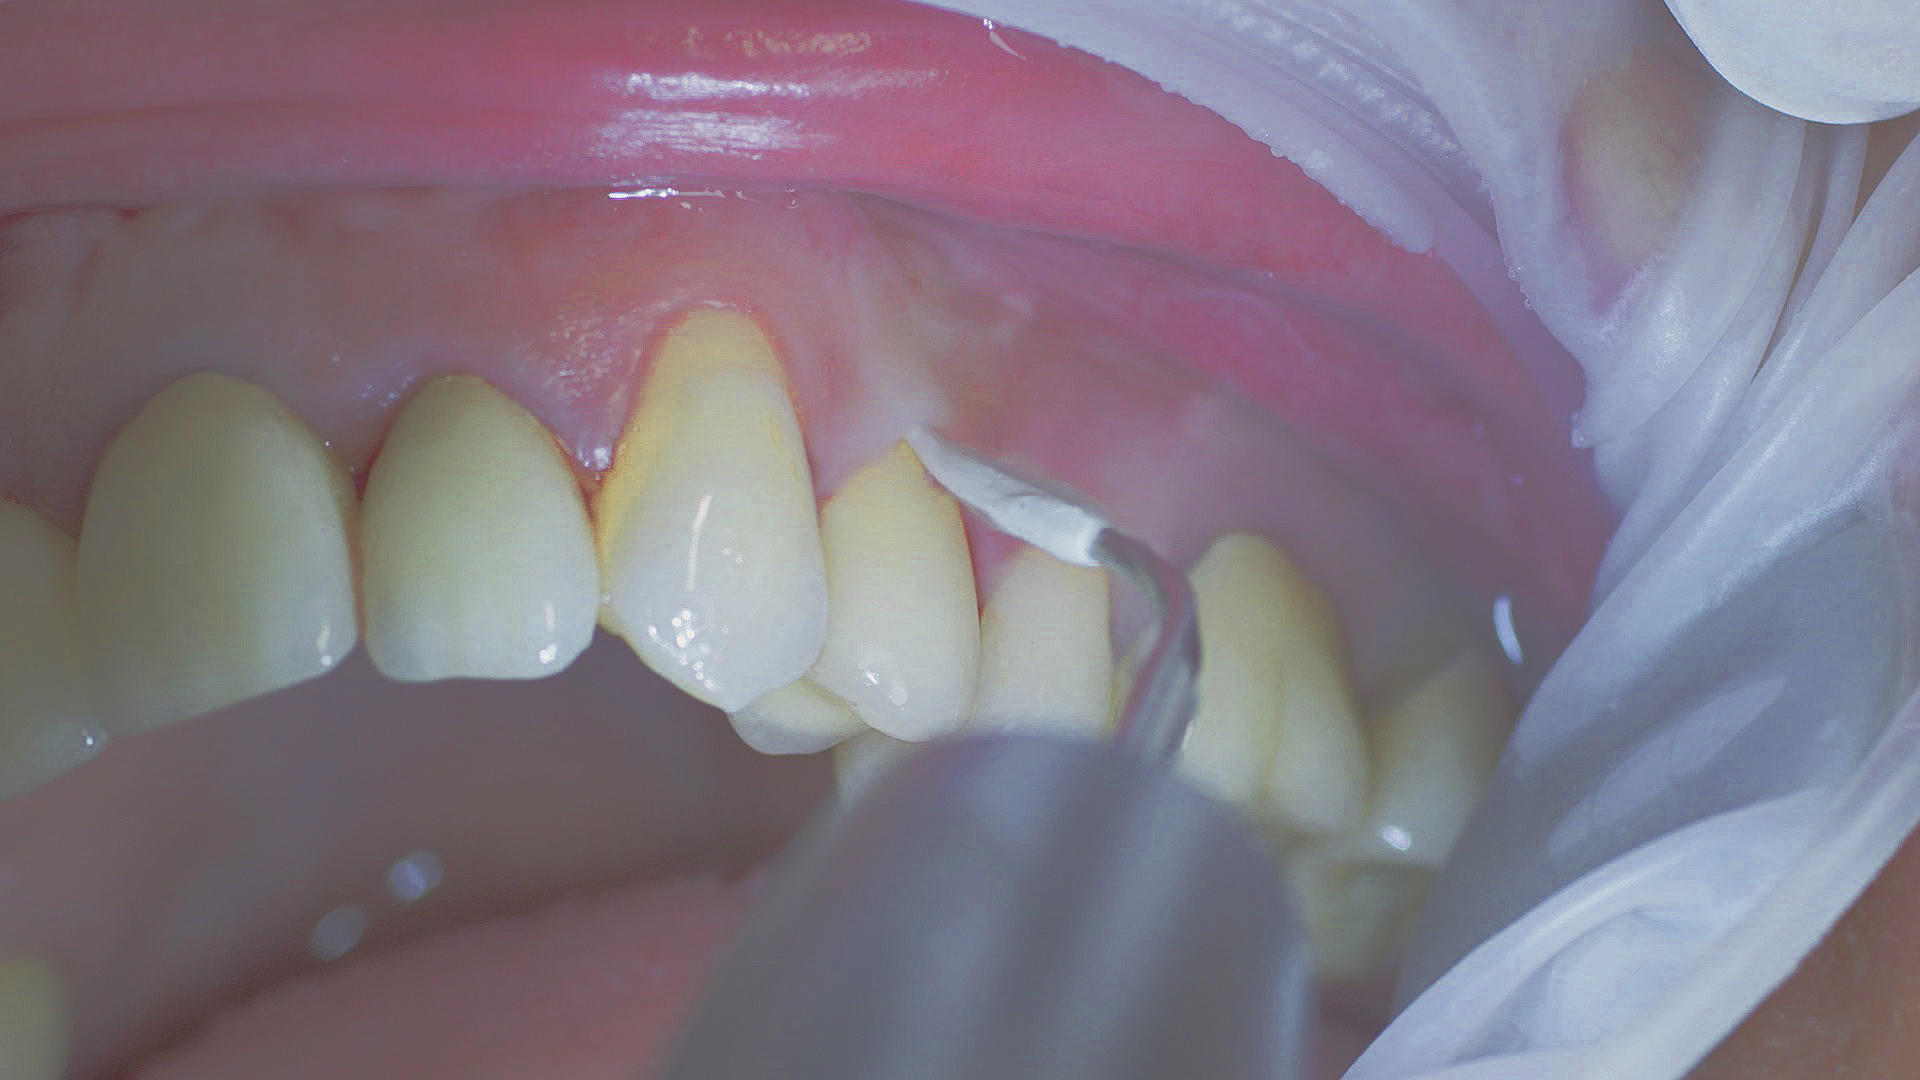

Healthy peri-implant tissue does not show any signs of redness, swelling or bleeding, neither does it secrete pus when probed.[5] Based on the consensus document, Prof. Giovanni Salvi explained the importance of regu- lar probing — preferably with a flexible probe, as implant components often tend to obstruct the procedure.[5] In the case of mucositis or initial peri-implantitis already being present, the non-surgical removal of hard deposits and biofilm should be attempted first. For this purpose, ultra- sonic power and special instruments designed to protect the implant should be employed (Fig. 3; piezo scaler Tigon+ with 1I, W&H). In case of no remission, the recall frequency needs to be increased. However, specific recommendations, applicable to individual cases, are not yet available in this context.[15]